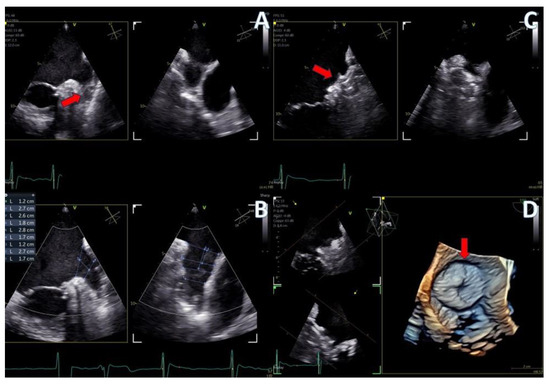

Figure 4.

(A) A 4D demonstration of a true−bicuspid aortic valve (red arrow), (B) Biplane 2D demonstration of a true−bicuspid aortic valve (red arrow), (C) Chronic dissection of descending aorta (red arrow showing the wall of the true lumen), (D) 3D volume-rendered color Doppler image showing the true (right arrow) and the false lumen (left arrow).

The imaging capabilities of the 4D mini-TEE probe were consistently excellent across all procedures (Figure 5, Figure 6, Figure 7, Figure 8 and Figure 9). Trans-septal puncture in ablation cases was facilitated by biplane imaging (Figure 5), demonstrating a nice tending of the septum. For the guidance of wires to the pulmonary veins, both 2D and 4D volume-rendered images were utilized (Figure 5 and Figure 6), expediting the procedure. The TEE probe was removed after the insertion of the cryo-ablation catheter into the LA.

Secundum ASD closure case; (A) Flexislice method for measurements with both 2D and 4D images, (B) guide catheter through the defect (red arrow), (C) biplane 2D images showing the implanted ASD occluder, (D) 3D volume-−rendered image showing the final result with an ASD occluder.

Figure 8.

LAA closure case; (A) biplane images of the LAA showing the presence of distal thrombus (red arrow), (B) measurements of the ostium and the landing zone with biplane imaging, (C) Biplane images of the implanted AMULET device (red arrow), (D) 3D volume−rendered image showing a view of the implanted AMULET device (red arrow).

Figure 9.

PFO closure case; (A) J wire through the PFO tunnel (red arrow), (B) stiff wire for guidance through the PFO tunnel (red arrow), (C) 3D volume−rendered view of the guide catheter through the PFO tunnel (red arrow), (D) final result with left atrial view of the PFO Amplatzer occluder (red arrow).

In the case of LAA closure (Figure 8, video S3), 3D tools (MPR-flexislice) aided in accurate sizing of the ostium and the landing zone (important for AMULET device), particularly in the presence of distal thrombus where contrast infusion was contraindicated. The final result was satisfactory, with no leakage observed and a stable device placement was confirmed with a tug test.

PFO closure cases (Figure 9, video S2) benefited from the probe’s excellent imaging, enabling precise wire insertion and providing anatomical criteria for device sizing. A bubble contrast study was performed at the beginning and at the end of the procedure for any remaining shunt. The stability of the device was confirmed with a wiggle test. Similarly, in the ASD case (Figure 7, video S1), the probe facilitated visualization of all defect rims and accurate sizing of the oval-shaped defect (with MPR) confirmed with balloon sizing and stop-flow technique and ensured a successful outcome with no residual shunt observed.